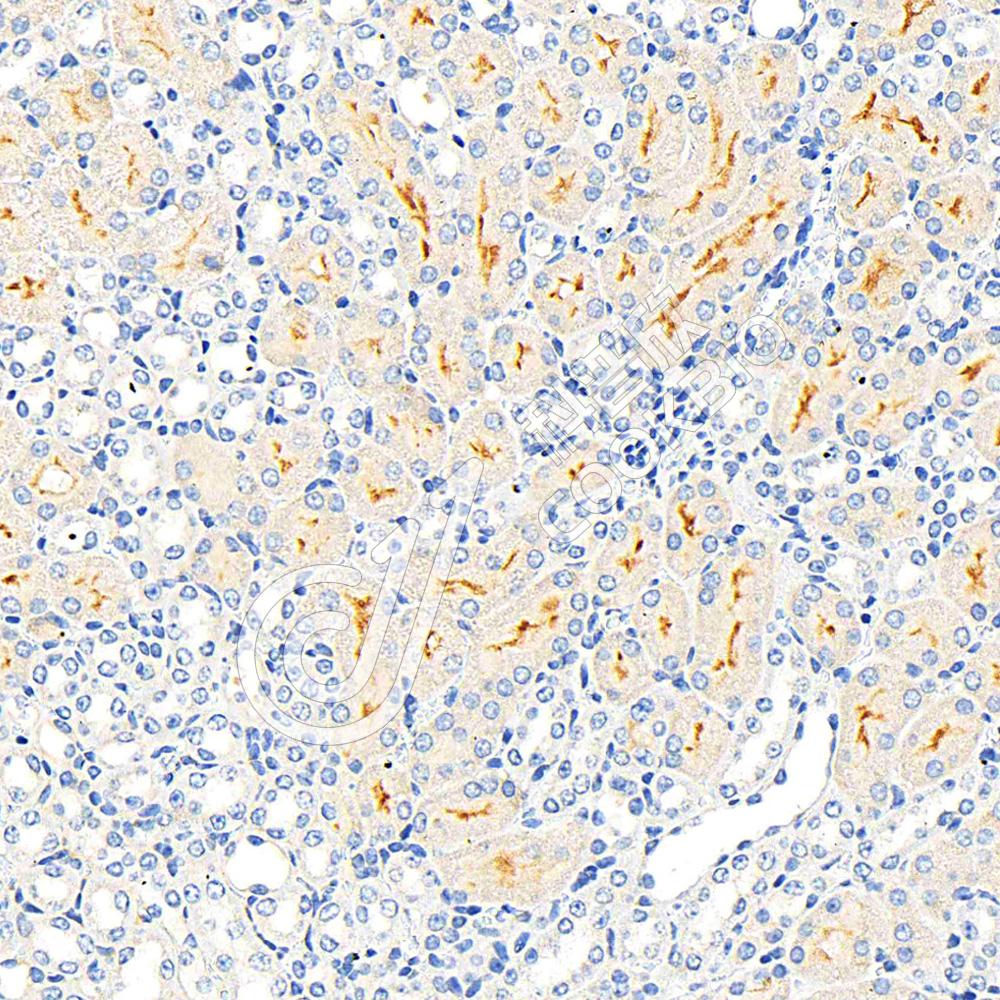

IHC检测PSMA蛋白(货号 K1347130).

样品: 小鼠肾, 4%多聚甲醛 (货号KSG1101) 固定12-24小时.

抗原修复: 柠檬酸抗原修复液(干粉, pH 6.0) (KSG1201), 高压锅均匀喷气计时2分钟.

—抗: 1: 300稀释, 4℃ 孵育过夜.

二抗: S-vision免疫组化多聚二抗(山羊抗兔),即用型 (货号KB3906), 室温孵育20分钟.